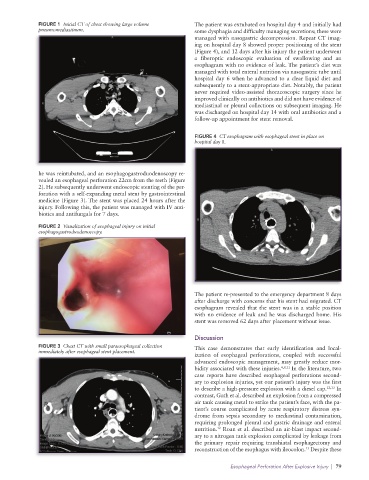

leading to severe inflammation, infection, and mediastinitis. 1 emphysema in the lower neck and mediastinum and a large

Esophageal injuries have reported mortality rates ranging volume pneumomediastinum on initial chest CT (Figure 1).

from 10% to 40%, with early recognition and intervention The patient was intubated for airway protection.